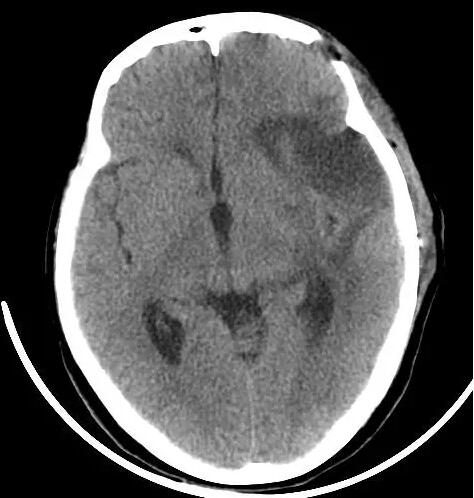

术前头部MRI显示为左外侧裂占位,血运丰富